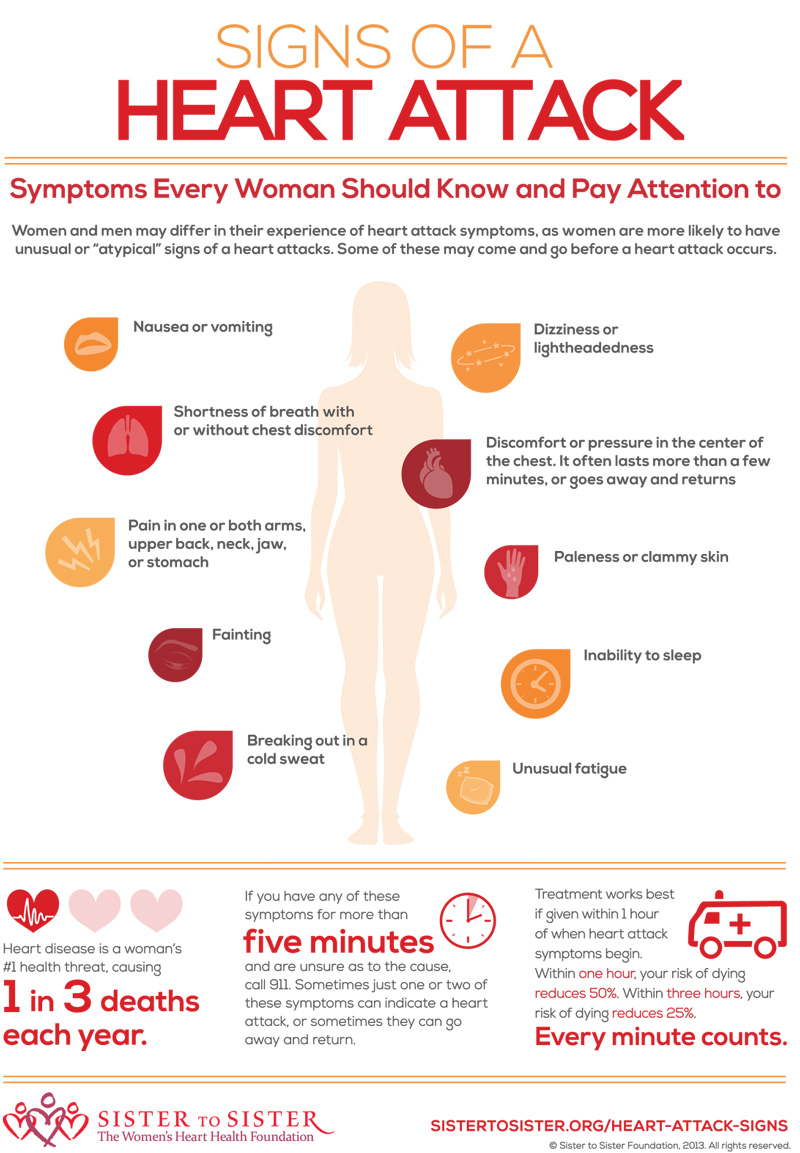

What Medication To Give During Heart Attack

What Medication To Give During Heart Attack

It Is Common Knowledge That The Symptoms Of Heart Attack Can Be

More picture related to What Medication To Give During Heart Attack

Heart Attack Symptoms

Heart Attack Woman Disease Symptoms Medical Illustration

Heart Attack Woman Disease Symptoms Medical Illustration

Heart Attack Signs And Symptoms

What Medication To Give During Heart Attack - [desc-12]